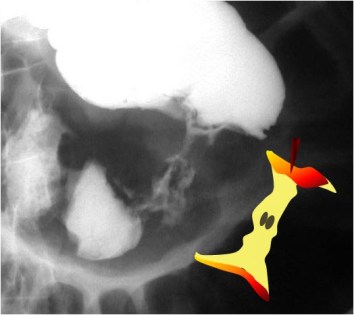

SIGNO DEL COLON RAYADO

Los implantes metastásicos en la serosa del colon producen una reacción desmoplásica causante de la rigidez y retracción de la pared del colon, que se manifiesta por estrías o pliegues transversales en el colon, en el estudio con doble contraste (flechas).

Esta imagen muestra la afectación similar en un asa de intestino delgado.

El artículo de referencia es de S Ginaldi, MM Lindell, Jr y J Zornoza en AJR de 1980: The striped colon: a new radiographic observation in metastatic serosal implants. Disponible en: http://www.ajronline.org/doi/pdf/10.2214/ajr.134.3.453.